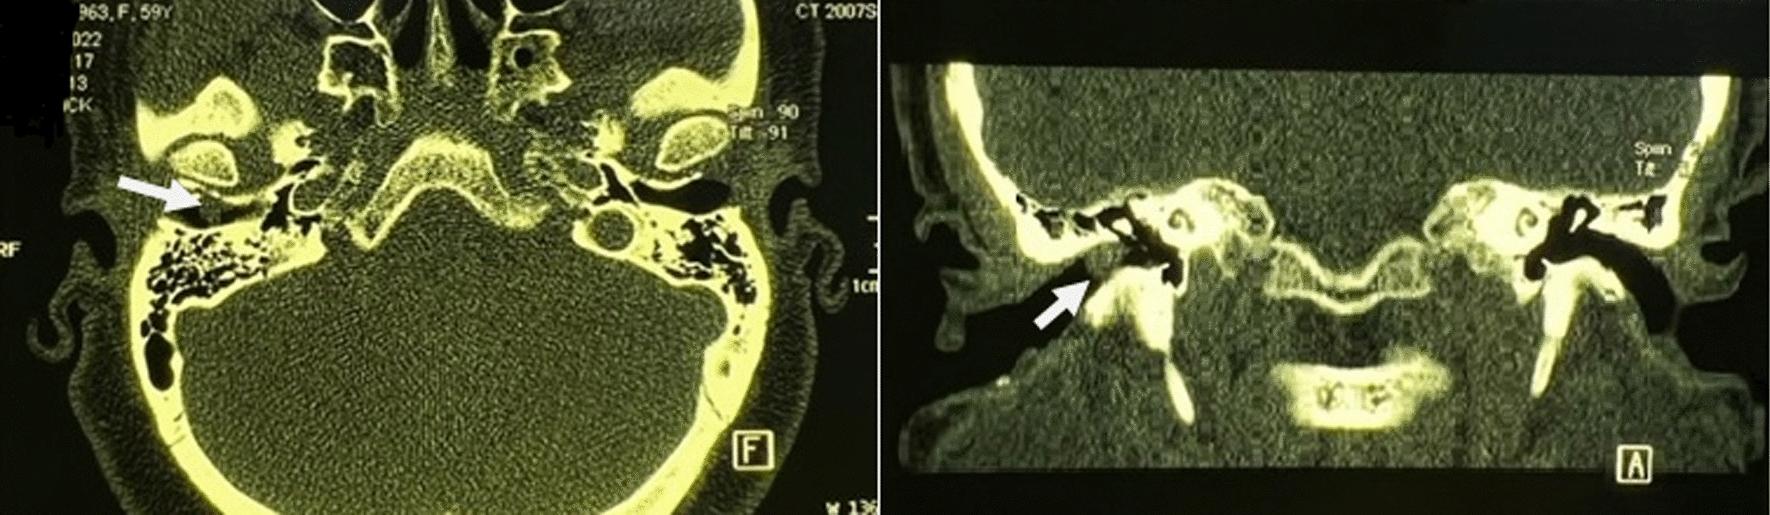

We report a 60-year-old Persian woman with an incidentally discovered painless fibroepithelial polyp in the right external auditory canal. Microscopic transcanal surgery confirmed the diagnosis after temporal computed tomography imaging showed a soft tissue mass.

我们报告了一例 60 岁的波斯女性,在右侧外耳道偶然发现无痛性纤维上皮息肉。颞骨计算机断层扫描成像显示软组织肿块后,经经耳道显微镜手术确诊。